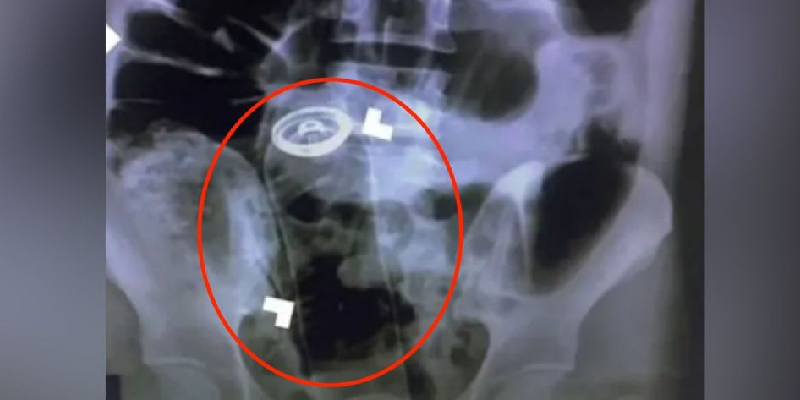

Creyó que estaba estreñido; le encuentran un desodorante en el recto